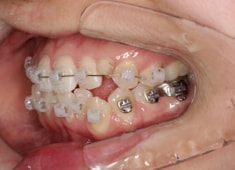

治療後(2年9ヶ月後)